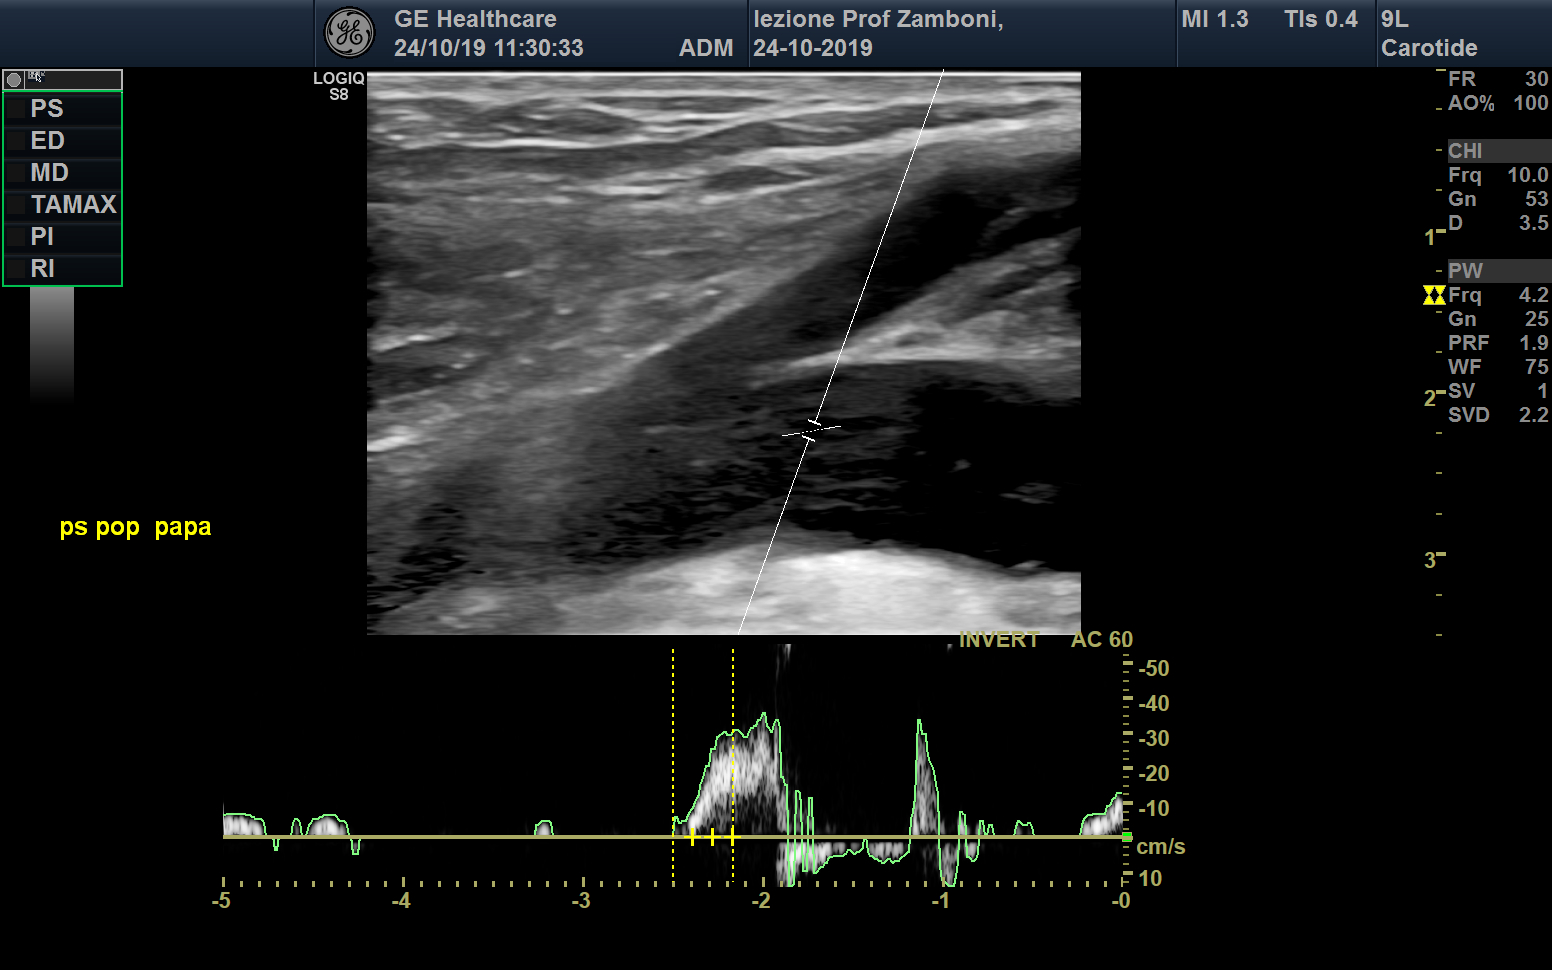

PW V. Poplitea Paranà

JPEG image icon PW V. Poplitea Paranà.jpg — JPEG image, 514 kB (526429 bytes)